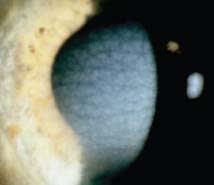

It is said that a picture is worth a thousand words; the best way to diagnose a corneal dystrophy is often to compare the eye that you see with images of diagnosed corneal dystrophies. This allows you to match the cornea that you are examining to a variety of images to ensure the proper diagnosis. Figures 1 through 24 can be considered good examples of many of the dystrophies listed in the tables and may be a useful reference in making a diagnosis. All of these figures except for Figure 12 originally appeared in the December 2008 supplement of the journal Cornea and are reprinted with permission of The Cornea Society, Copyright 2008, all rights reserved.

![]() Figure 11. Granular corneal dystrophy type 1. type 2 (granular lattice). |